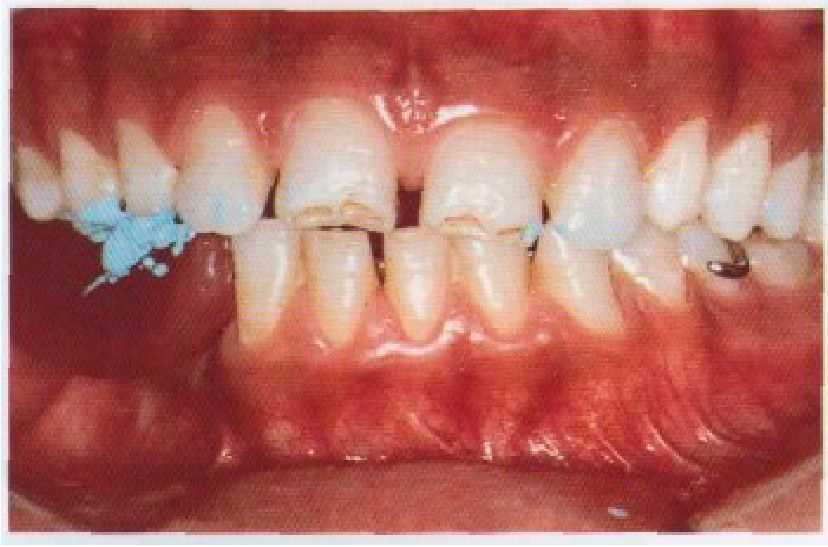

Рис. 11-6. Окончательная регистрация центральной окклюзии, как указывалось выше. Имеют место нормальные межзубные контак ты, и элементы съемного протеза подогнаны так, что накладки и кламмерные плечи не создают помех правильным окклюзионным взаимоотношениям.